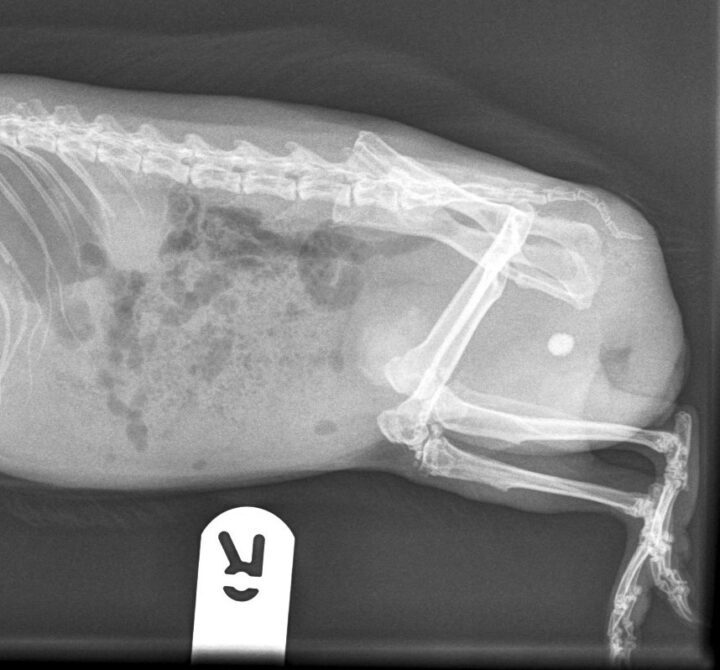

Diagnosis is typically based on clinical signs, physical examination, urinalysis and imaging. The urine may appear cloudy or contain visible sediment. Radiographs can help assess the amount of sludge present and rule out other issues such as urolithiasis (Figure 2). Urinary ultrasound is another useful tool, providing a more detailed view of the bladder wall and sludge accumulation.

The clinical signs of urolithiasis in rabbits include haematuria, dysuria, frequent urination and stranguria. In some cases, the stones can cause a complete obstruction of the urinary tract, which is a medical emergency (Circella et al., 2021). Diagnosis is confirmed through radiographs, where the stones will appear as radiopaque structures, or via ultrasound, where uroliths result in acoustic shadowing.

Common symptoms of urolithiasis in guinea pigs include stranguria, haematuria and signs of discomfort or pain when urinating, such as vocalisation. Diagnosis of urolithiasis in guinea pigs is similar to diagnosis in rabbits, using physical examination, urinalysis and imaging techniques, such as radiographs or ultrasound. Radiographs will often reveal the presence of stones (Figure 4), though small stones may be missed if they are not radiopaque. Ultrasound can be particularly useful for detecting smaller stones or those located in the kidneys or ureters.

Diagnosis is achieved through radiographs, ultrasound and urinalysis in the same way as rabbit and guinea pig patients. Radiographs will typically reveal the presence of radiopaque stones, while ultrasound can help identify smaller or less visible stones. Urinalysis may show the presence of crystals, bacteria or blood. Surgical cystocentesis to remove the stone is often the treatment of choice. Following removal of the stone, submitting the sample for culture and composition analysis may prove useful in treatment. Prevention of further urolithiasis formation involves dietary modification by transitioning the patient to an animal-protein-based diet and increasing water intake.